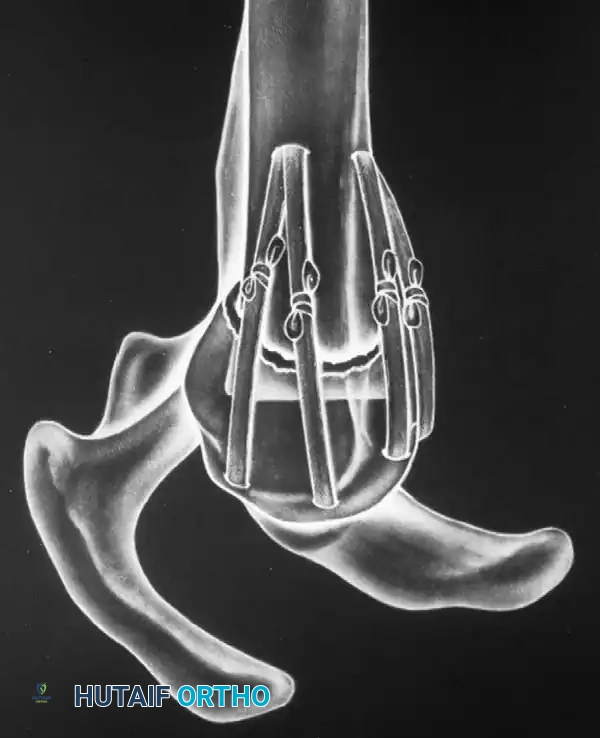

Transosseous Suture Fixation

Transosseous suture fixation techniques are well-defined and highly effective, particularly in osteoporotic bone where metal hardware may cut out. Park et al. reported 78% excellent results in patients with two-part and three-part fractures treated with this method.

Clinical Pearl: The use of heavy, nonabsorbable sutures allows the surgeon to incorporate the robust rotator cuff insertions (supraspinatus/infraspinatus for the greater tuberosity; subscapularis for the lesser tuberosity) to neutralize deforming muscle forces and secure the tuberosity fragments.

This technique requires minimal soft-tissue stripping, preserving the delicate vascular envelope and resulting in relatively low rates of osteonecrosis. However, the construct is inherently less rigid than locked plating, requiring careful patient compliance during early rehabilitation to prevent loss of reduction.

Fig. 54-13 Transosseous nonabsorbable sutures incorporate rotator cuff to increase fi xation and help control tuberosity fragments.